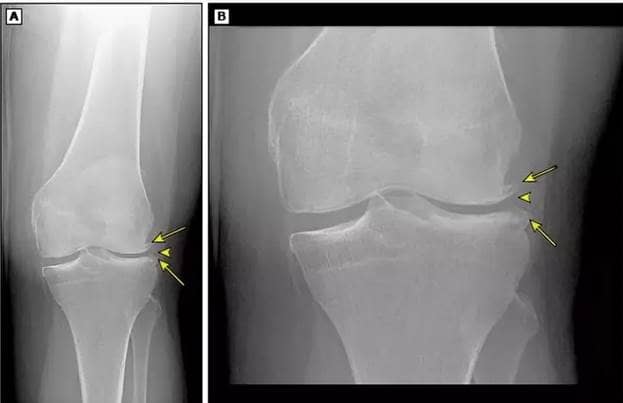

Narośle kostne w stawie kolanowym